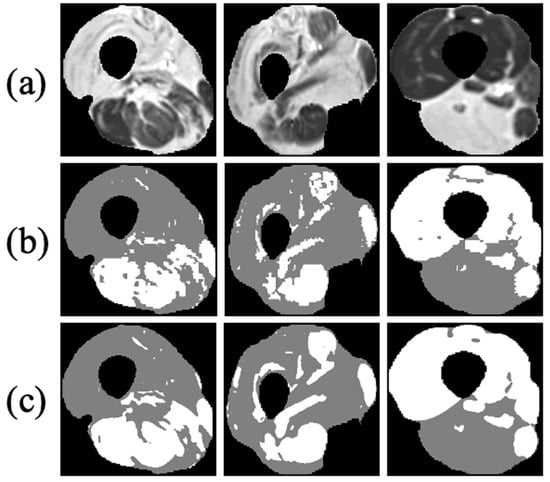

2.2.1. Bias Field Removal

MRI receiver coils have an inherently inhomogeneous spatial sensitivity profiles, causing a bias field (B1) in the images. This effect was corrected by using the N4ITK method [30]. The input to this step is a series of T2 weighted images, sampled at increasing echo times and for different slice locations, while the correction was applied separately for each slice. The method was implemented in 3D Slicer (http://www.slicer.org accessed on 1 February 2022) [31]. Figure 3 shows an input image (left) that was contaminated with an inhomogeneous bias field (middle) causing a nonphysiological variation in the signal intensity to appear at the bottom of the image. The right panel demonstrates how this bias field can be effectively removed, resulting in a more homogeneous depiction of the imaged anatomy.

Figure 3. Correcting receiver gain bias in an axial MRI of the calf. Left: Image affected by inhomogeneous B1 intensity bias; Middle: bias field, estimated using the N4ITK method; Right: image after intensity correction.